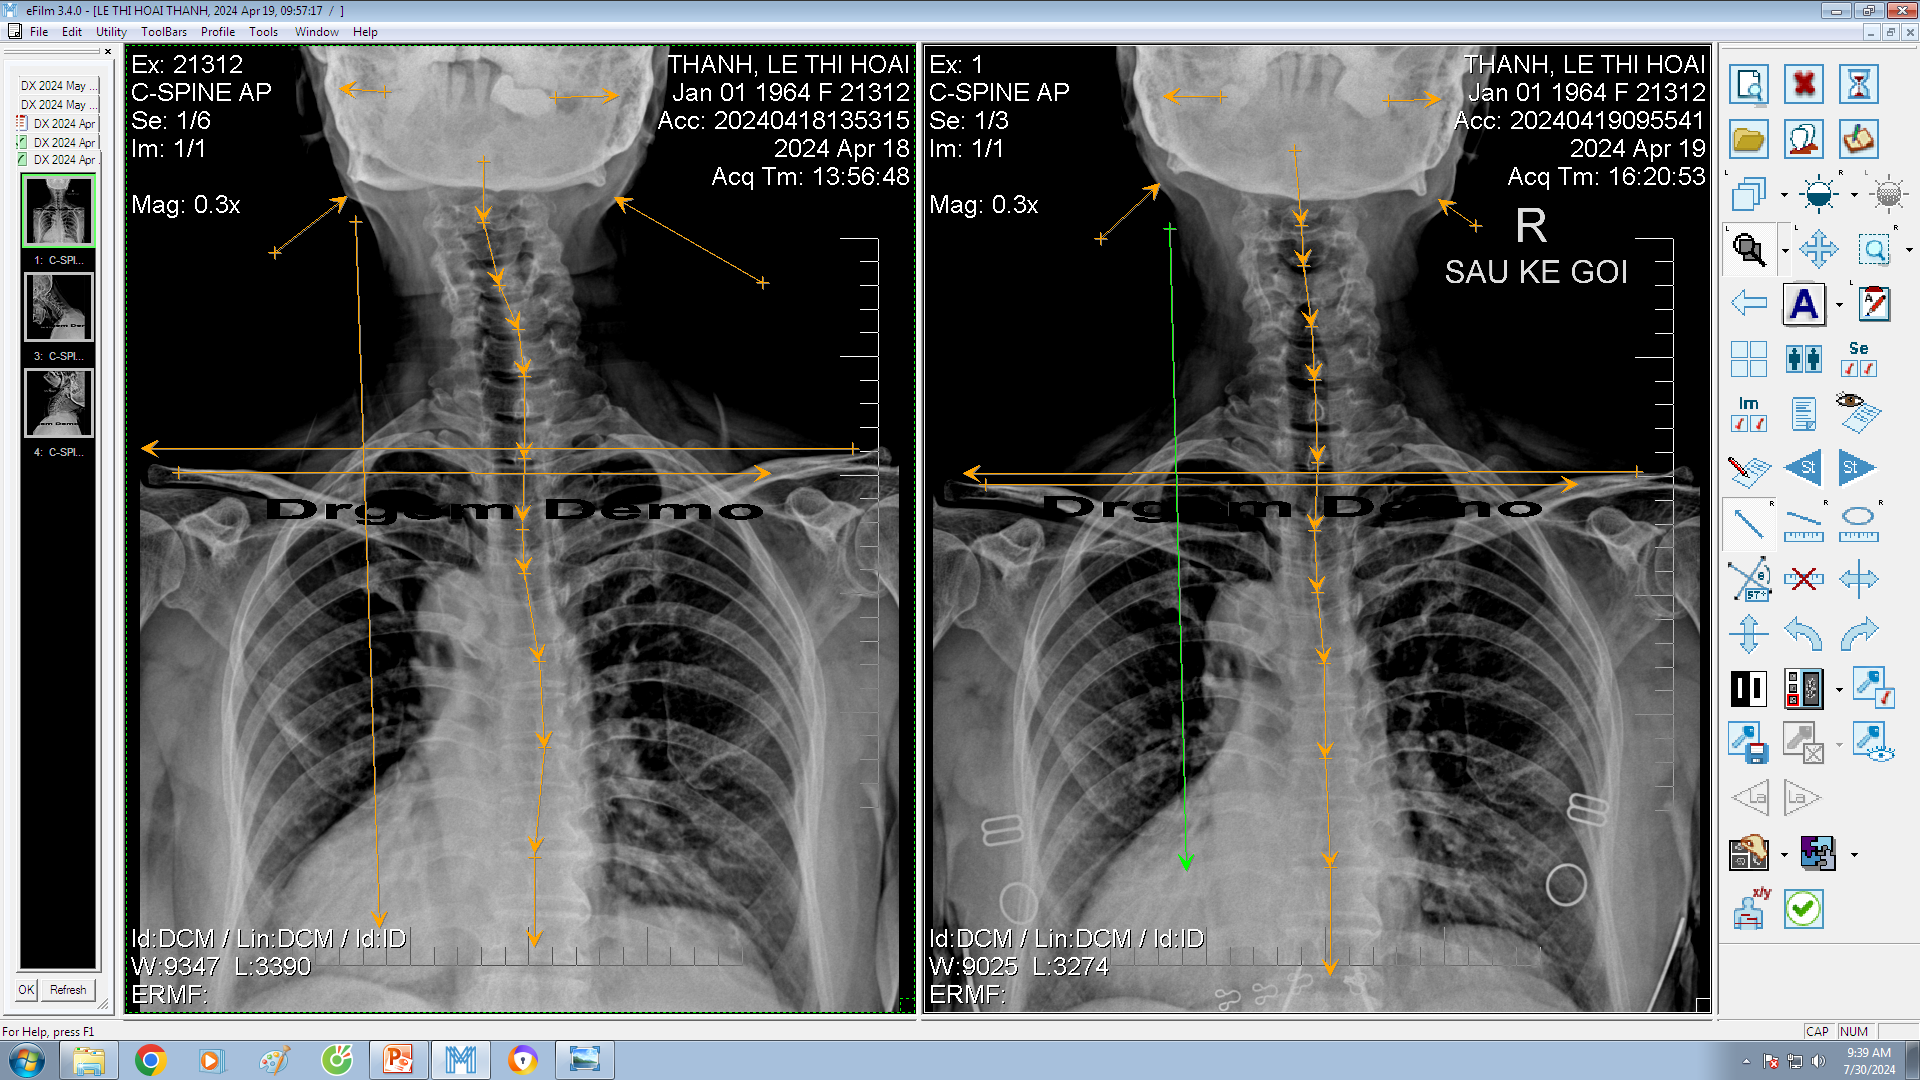

DOCTORLOAN đã thành công trong điều chỉnh xương khớp về đúng vị trí trong thời gian ngắn